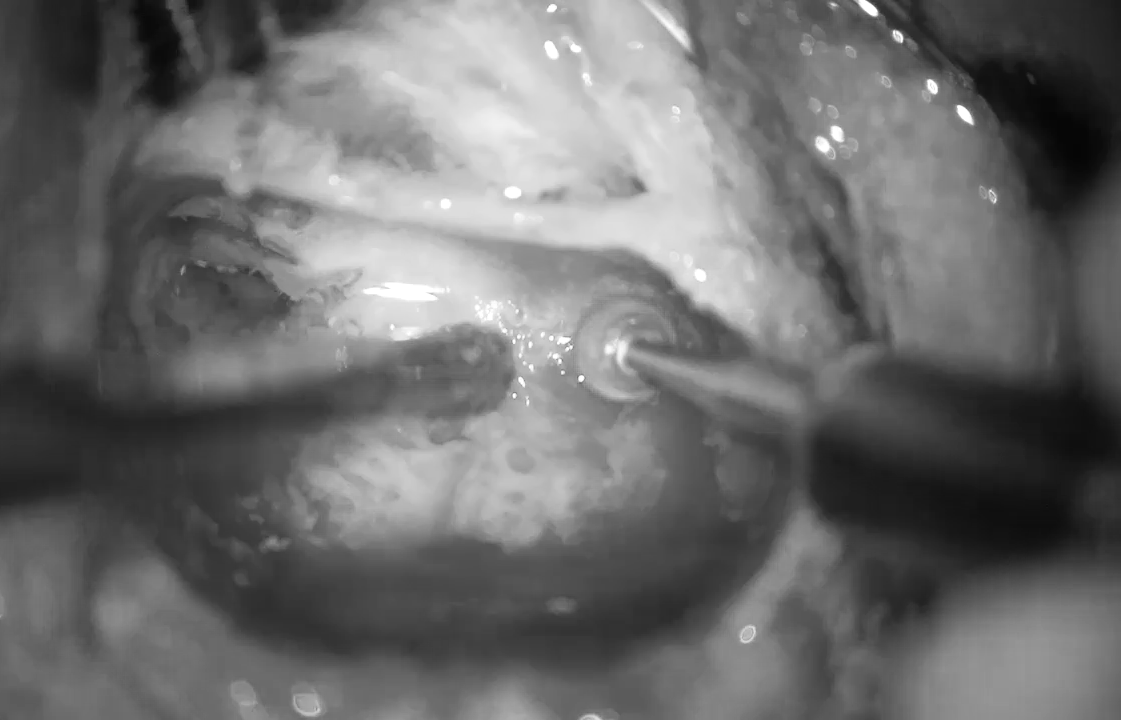

Ca phẫu thuật cấy ốc tai điện tử trở nên nhẹ nhàng hơn khi chuẩn bị kỹ về CT Scan, ảnh BVCC

Ca phẫu thuật cấy ốc tai điện tử trở nên nhẹ nhàng hơn khi chuẩn bị kỹ về CT Scan. Ảnh: BVCC

Hiện nay, phẫu thuật cấy ốc tai điện tử là một trong những tiến bộ nổi bật, được FDA chấp thuận để điều trị nghe kém. Tuy nhiên, đây là phẫu thuật khó, đòi hỏi bác sĩ phải thao tác trong vùng giải phẫu rất hẹp của tai giữa.

Đặc biệt khi tiếp cận màng cửa sổ tròn (vị trí quan trọng để đặt điện cực ốc tai), chỉ một khác biệt nhỏ về cấu trúc giải phẫu cũng có thể ảnh hưởng đến độ an toàn và kết quả phẫu thuật. Thế nên, chuẩn bị tốt từ hình ảnh CT Scan là bước quan trọng để ca mổ diễn ra an toàn, giúp trẻ sớm tiếp cận âm thanh.

CT Scan xương thái dương đóng vai trò như một “bản đồ” giúp phẫu thuật viên hiểu rõ cấu trúc tai giữa (tai trong trước khi mổ). Trong đó, ngách mặt (khoảng không gian nằm giữa dây thần kinh mặt và hòm nhĩ sau) là vùng then chốt quyết định việc bộc lộ màng cửa sổ tròn có thuận lợi để cấy ốc tai điện tử hay không, giúp “đoán trước” độ khó của ca mổ, giảm thiểu rủi ro trong quá trình phẫu thuật.